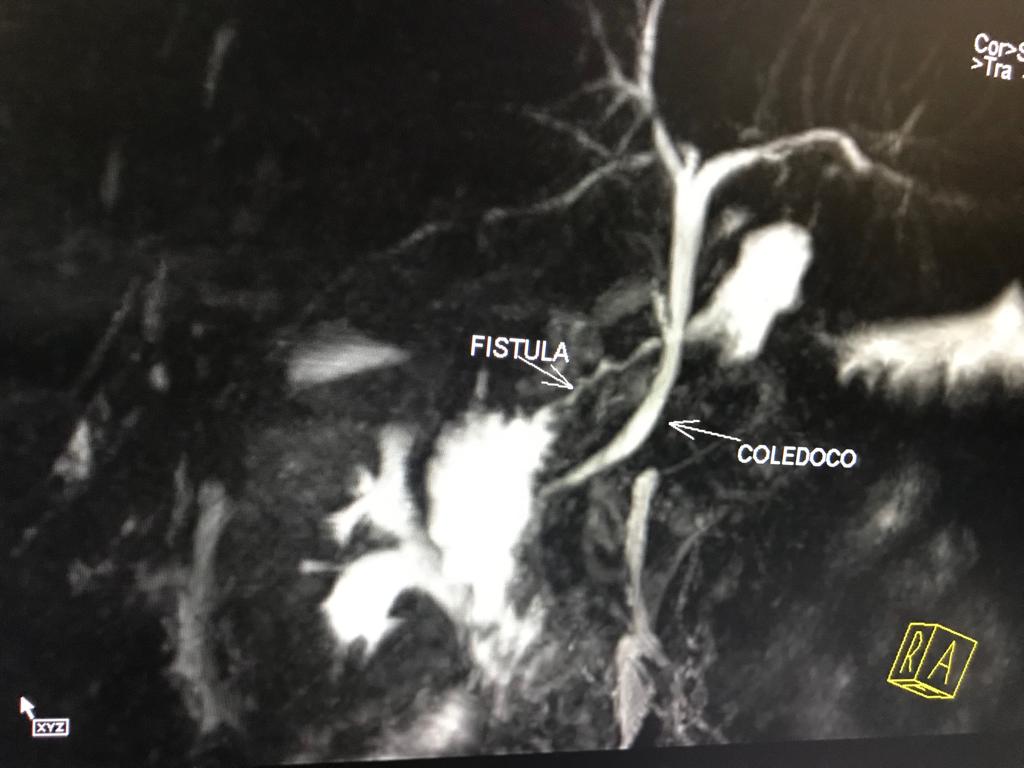

COLANGIORM Coledocolitiasis: Es la presencia de por lo menos un cálculo en el conducto colédoco. Dicho cálculo puede estar formado de pigmentos Biliares o de sales de calcio y de colesterol. Aproximadamente 1 de cada 7 personas con cálculos biliares, padece cálculos...